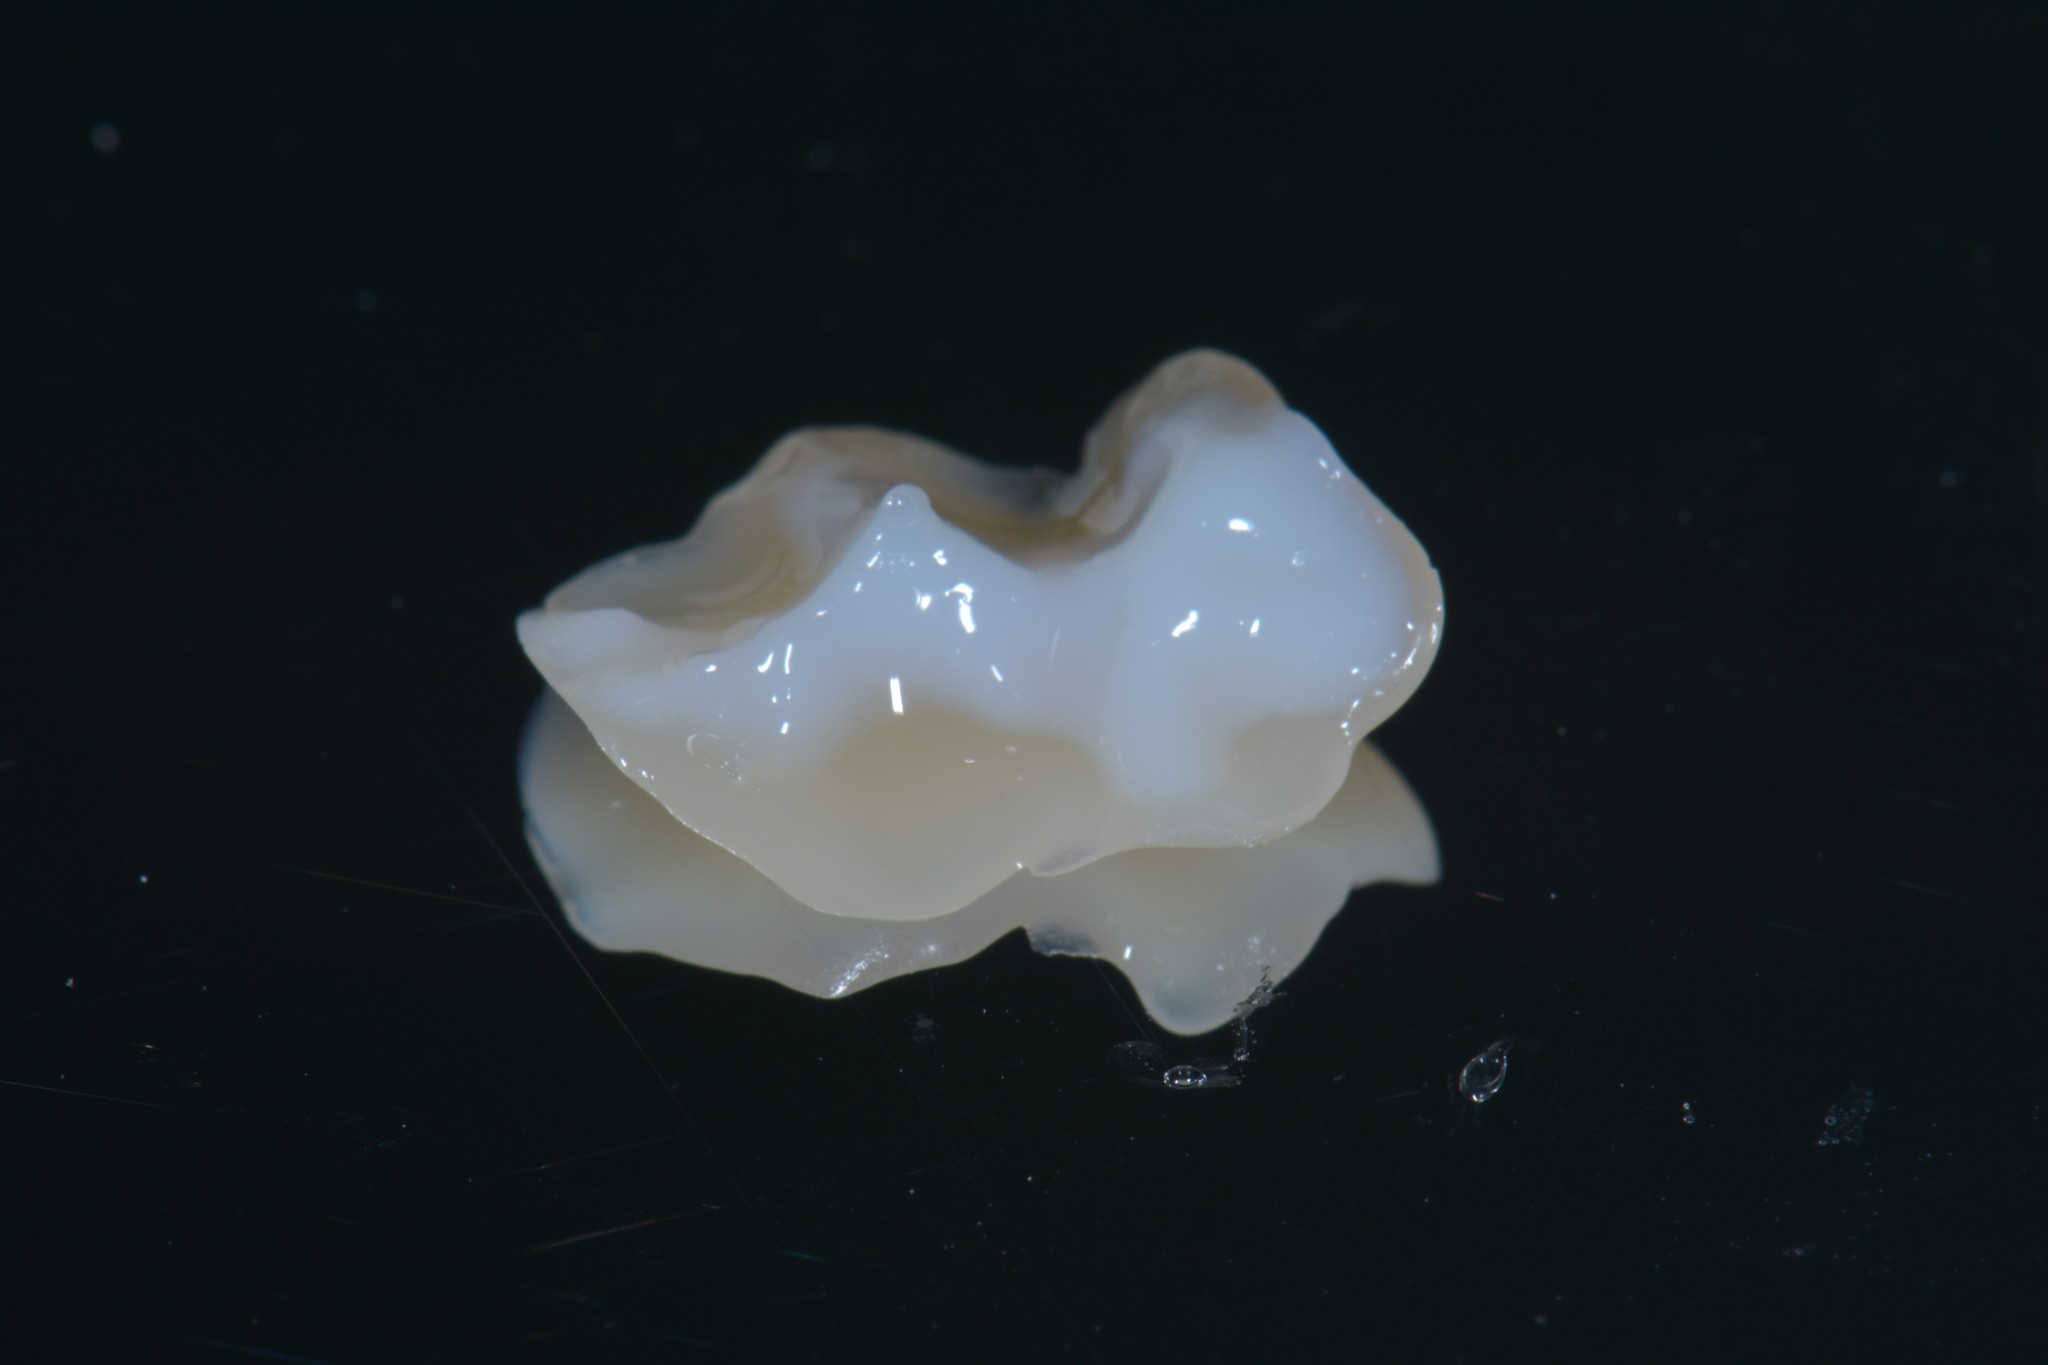

Un altro bellissimo utilizzo per il teflon è lo stampaggio del piano occlusale nelle otturazioni di prima classe (o se ti ingegni anche per le seconde classi) quando il dente da trattare conserva ancora la sua anatomia originale. In questi casi puoi utilizzare del sigillante dei solchi unitamente a del composito flow per creare lo stampo della superficie occlusale, poi, quando arrivi all’ultima applicazione di composito, lo distribuisci a riempimento della superficie occlusale, ci apponi sopra del teflon, premi lo stampo che avevi creato prima di iniziare a preparare la cavità e rimuovi il tutto tirando via il teflon. A questo punto si tratta solo di eliminare gli eccessi di composito e ritoccare leggermente i solchi et voilà! Hai riprodotto una bellissima anatomia che non richiederà praticamente alcun ritocco occlusale in pochi secondi!